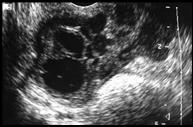

Bilateral tubo-ovarian abscesses with gas

Right                                                             Left